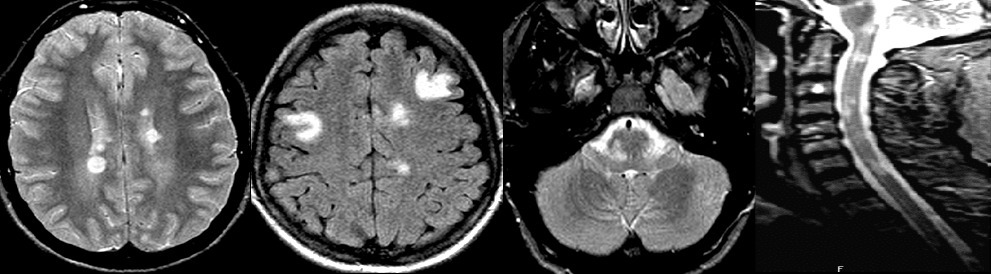

La dissémination spatiale est actuellement retenue s’il y a au moins une lésion IRM pondérée en T2/FLAIR dans au moins deux des quatre régions caractéristiques de la SEP (périventriculaire, corticale, sous-tentorielle, médullaire) [figure].

La présence de lésion(s) prenant le produit de contraste alors que d’autres ne le prennent pas, la présence d’une synthèse intrathécale d’immunoglobulines G, l’apparition de nouvelles lésions au cours du suivi IRM sont autant de critères faisant retenir la dissémination temporelle.